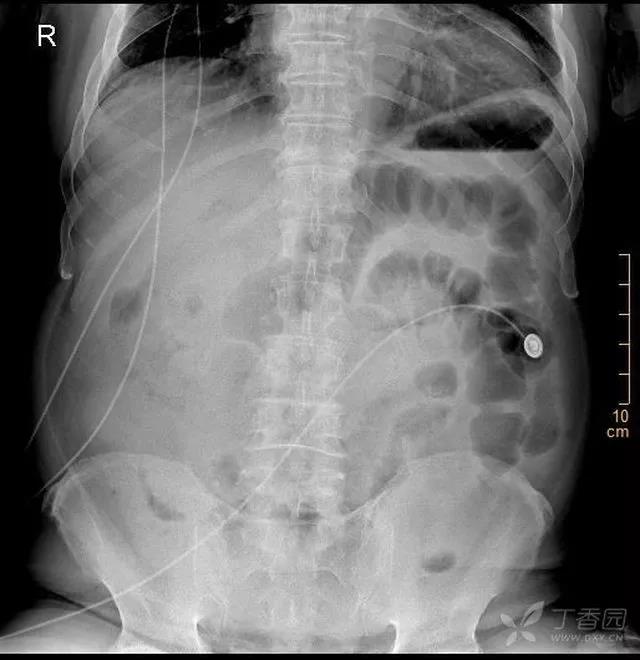

入院后,初步判断患者的症状重于体征和目前检查结果,先胃管,见黑色的胃液 350ml,立即申请增强 CT,需要等 CT 室的工作人员回来。

看看增强 CT 图片,能发现问题吗?

动脉期:

门静脉期:

入院后的相关检查结果:

结合现有资料,基本上可以明确诊断了,考考大家眼力!